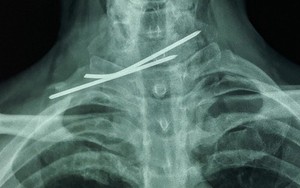

Cứu sống bệnh nhân bị đinh đâm xuyên thực quản và khí quản

Các bác sĩ của bệnh viện vừa cấp cứu thành công một ca bệnh rất nguy hiểm và hiếm gặp khi bệnh nhân bị 2 cây đinh Kirschner đâm xuyên thực quản và khí quản.